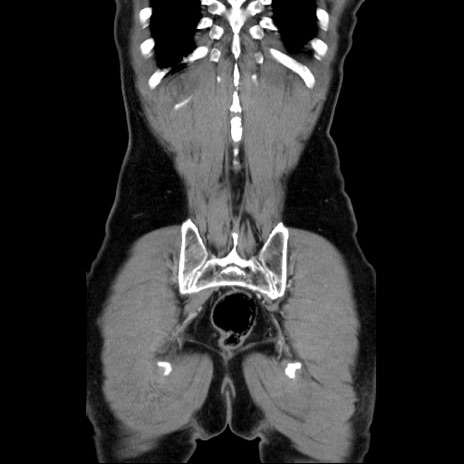

症例34(冠状断像)

【症例】60歳代 男性

【主訴】右鼠径部膨隆

【現病歴】1年程前より右鼠径部膨隆あり。自己にて還納可能だったため放置していた。3時間前より右鼠径部の脱出を認め、還納困難となり受診。

【既往歴】高血圧

【身体所見】右鼠径部に小児頭大の膨隆あり。弾性硬であり、用手還納は困難。左鼠径部にも膨隆を認める。脱出はなし。